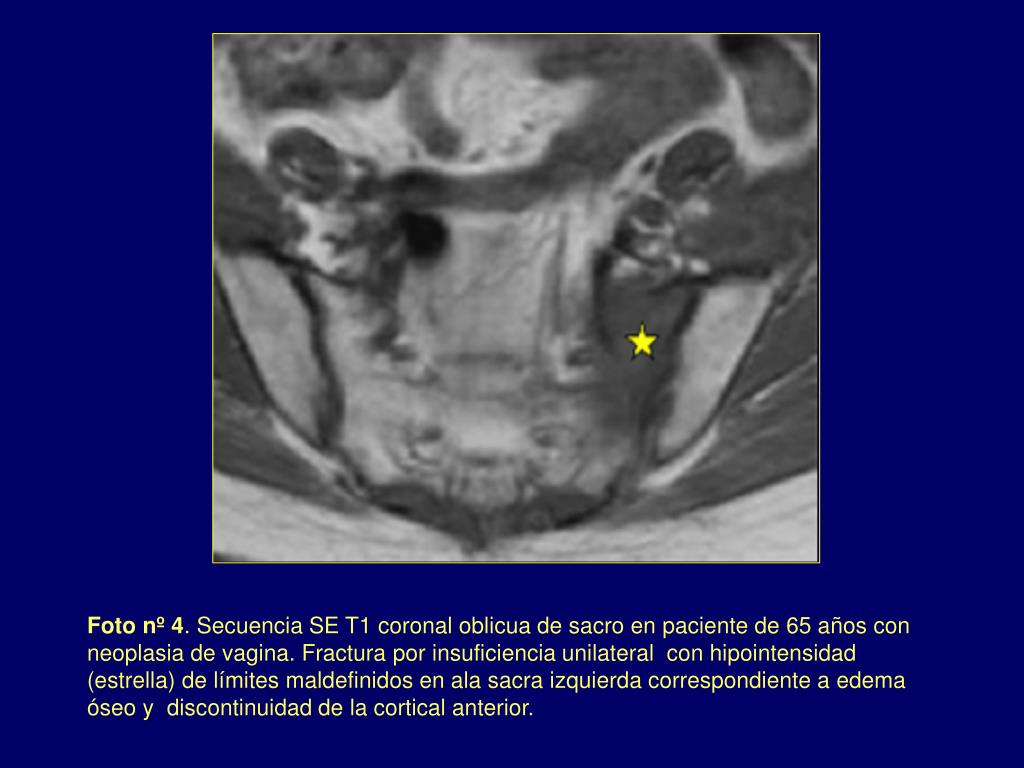

4. Foto nº 4. Secuencia SE T1 coronal oblicua de sacro en paciente de 65 años con neoplasia de vagina. Fractura por insuficiencia unilateral con hipointensidad (estrella) de límites maldefinidos en ala sacra izquierda correspondiente a edema óseo y discontinuidad de la cortical anterior.